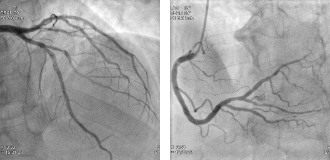

| 冠動脈画像(DR画像) | ||